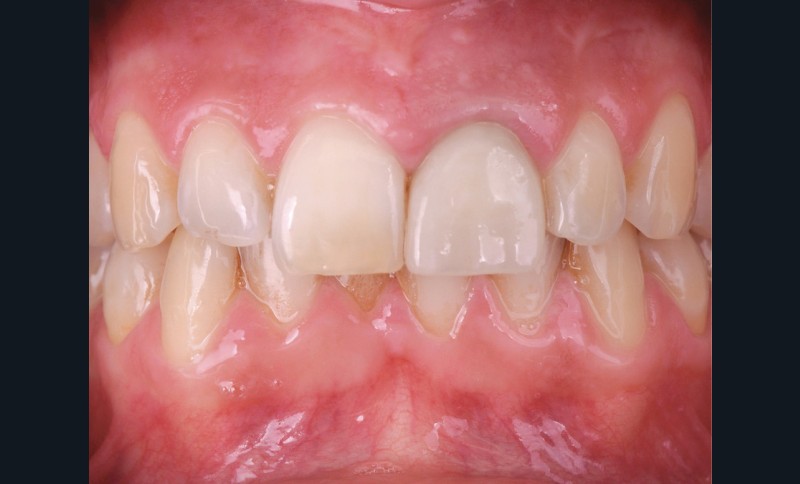

Une patiente de 32 ans est reçue en consultation au cabinet. Elle ne présente pas d’antécédents médicaux ou chirurgicaux. Elle se plaint de douleurs aiguës en regard de la 21 lors de la mastication. Cette dent a été traitée par son précédent chirurgien-dentiste il y a quinze ans, à la suite d’un accident de vélo. Un traitement endodontique a été rendue nécessaire ainsi que la pose d’un ancrage radiculaire de type inlay-core et d’une couronne céramo-métallique (fig. 1).

L’examen clinique révèle la présence d’un biotype parodontal épais, une gêne lors de la palpation vestibulaire ainsi qu’une douleur à la percussion. La réalisation d’une radiographie rétro-alvéolaire et d’un CBCT confirme la présence d’une fissure radiculaire (fig. 2).